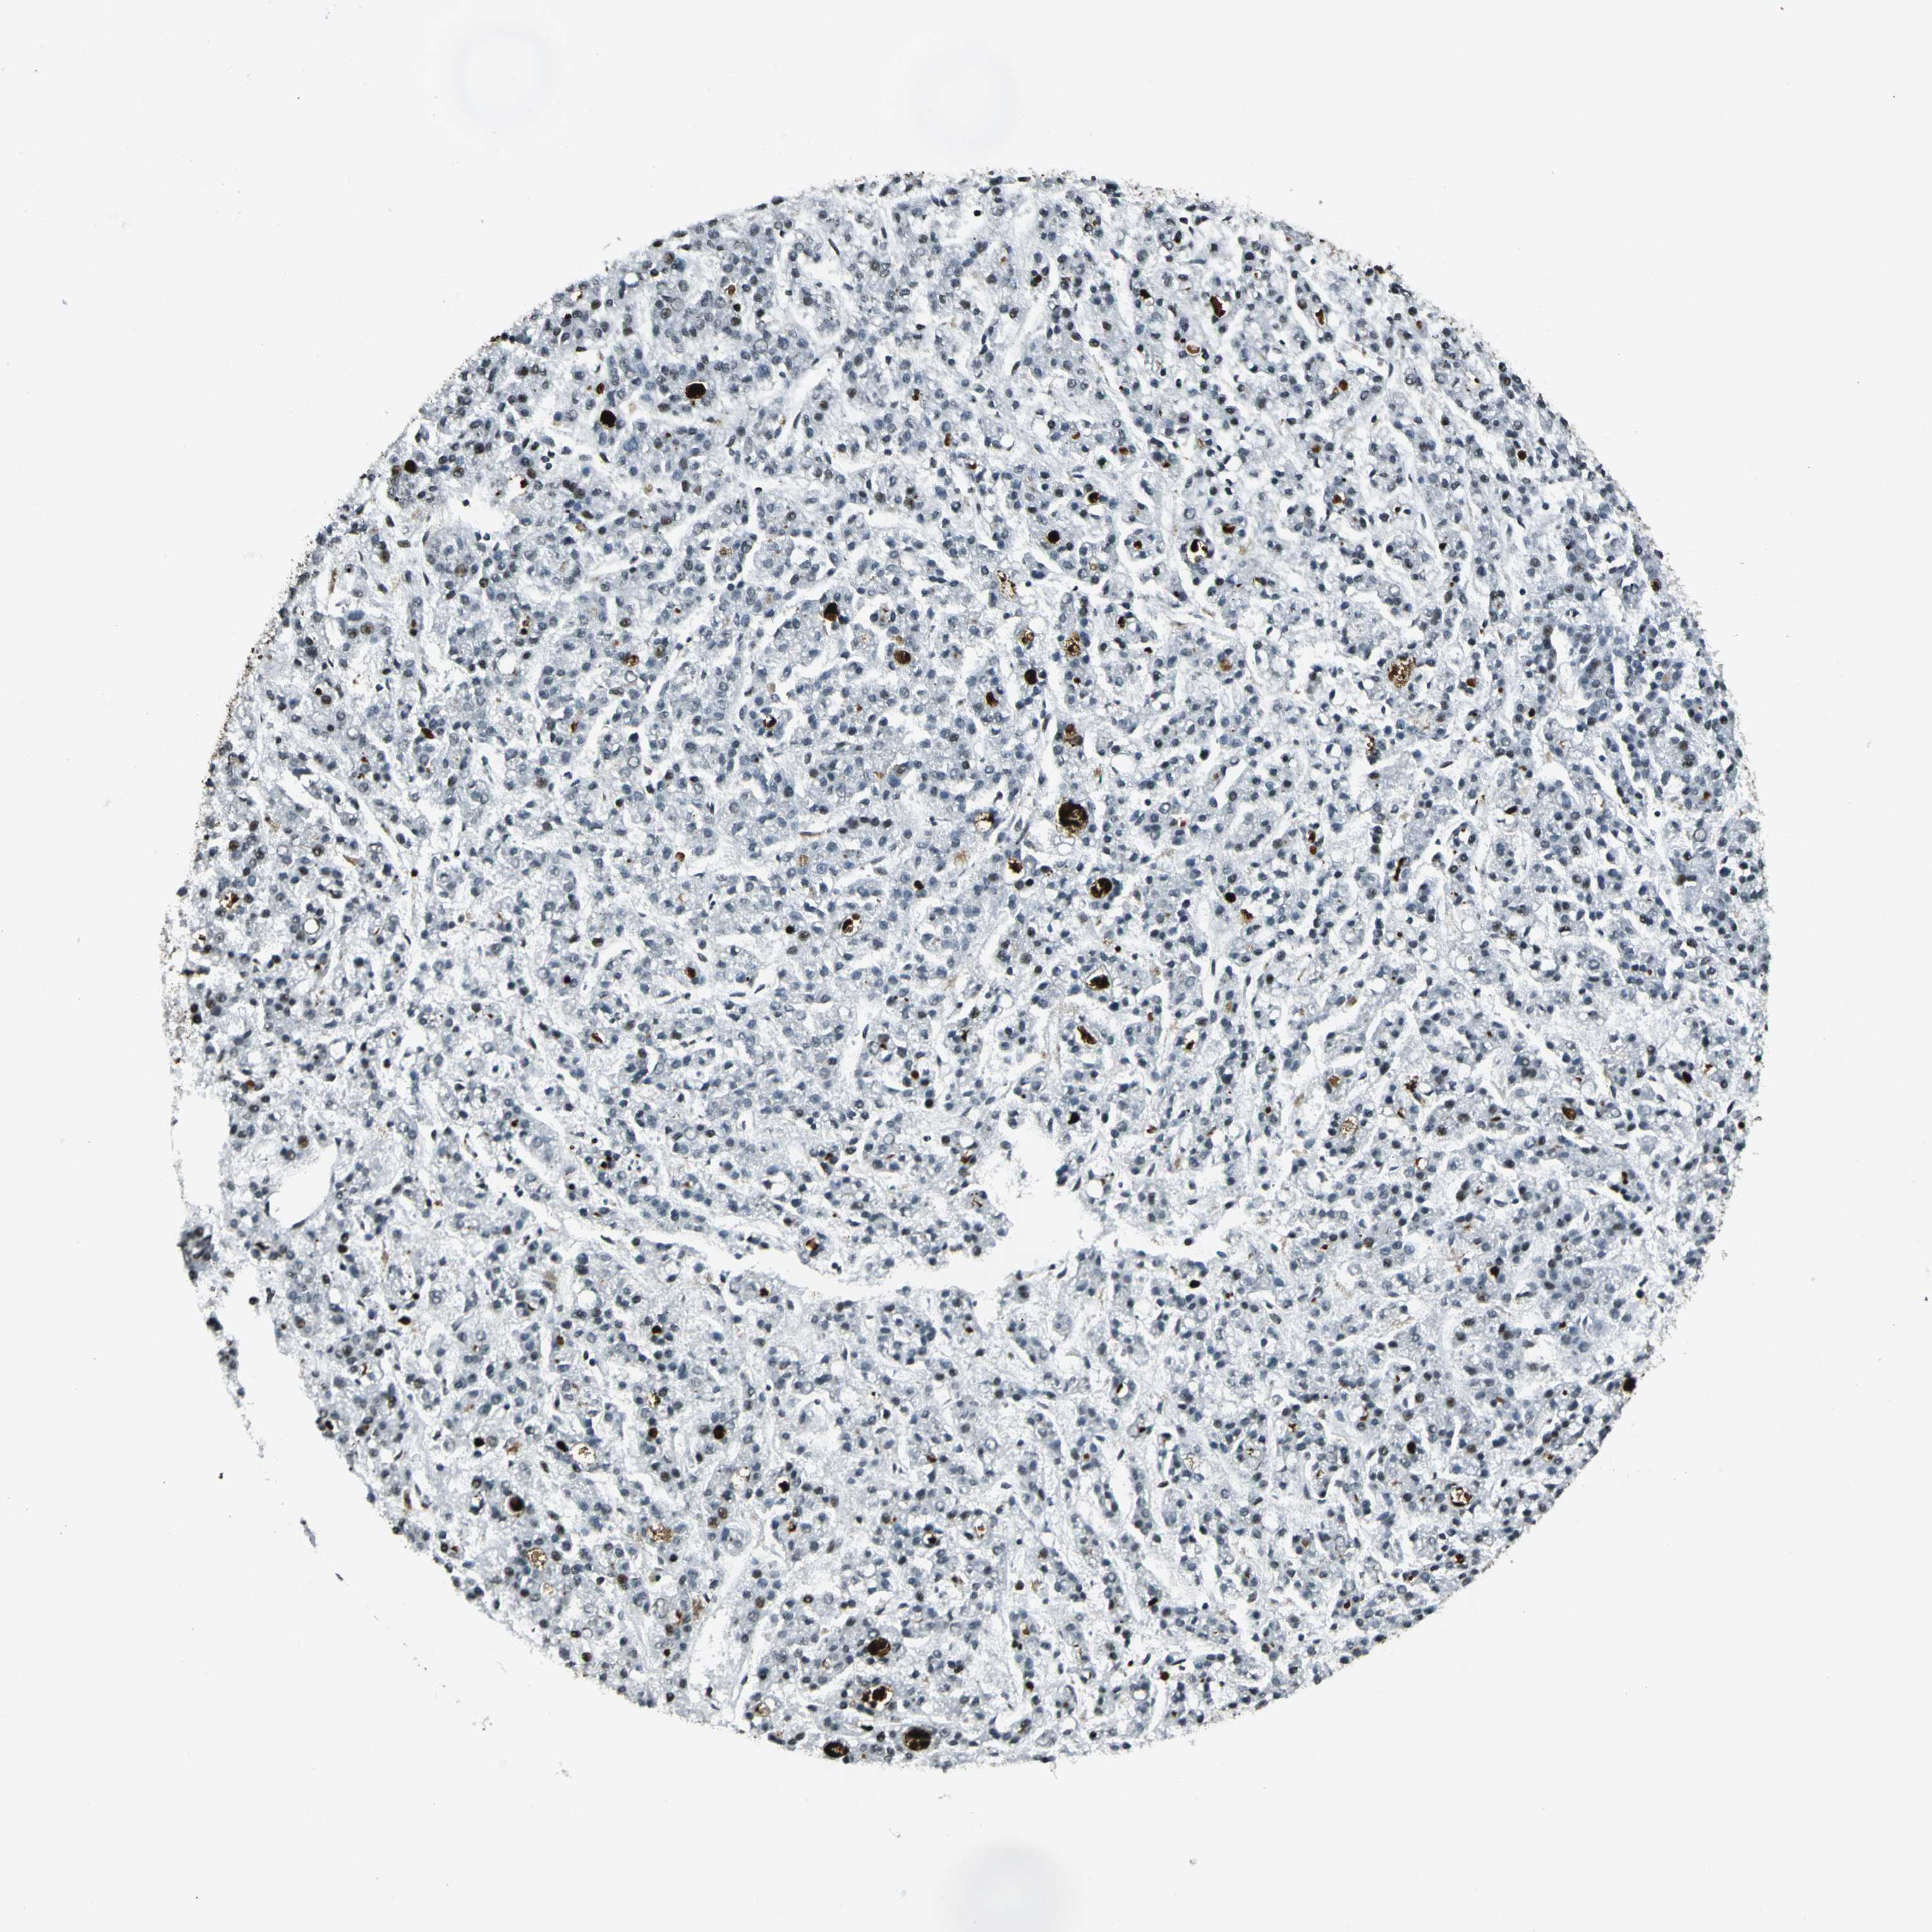

LIVER CANCER - Protein expressioni

A mouse-over function shows sample information and annotation data. Click on an image to view it in a full screen mode. Samples can be filtered based on level of antibody staining by selecting one or several of the following categories: high, medium, low and not detected. The assay and annotation is described here.

Note that samples used for immunohistochemistry by the Human Protein Atlas do not correspond to samples in the TCGA dataset.

Antibody stainingi

Antibody staining in the annotated cell types in the current human tissue is reported as not detected, low, medium, or high, based on conventional immunohistochemistry profiling in selected tissues. This score is based on the combination of the staining intensity and fraction of stained cells.

Each image is clickable and will lead to virtual microscopy that enables deeper exploration of all samples and also displays staining intensity scores, fraction scores and subcellular localization as well as patient and tissue information for each sample.

Antibody HPA004873

Antibody CAB004497

Staining

High

Medium

Low

Not detected

Intensity

Strong

Moderate

Weak

Negative

Quantity

>75%

75%-25%

<25%

None

Location

Nuclear

Cytoplasmic/membranous

Cytoplasmic/membranous,nuclear

Cholangiocarcinoma

Carcinoma, Hepatocellular, NOS